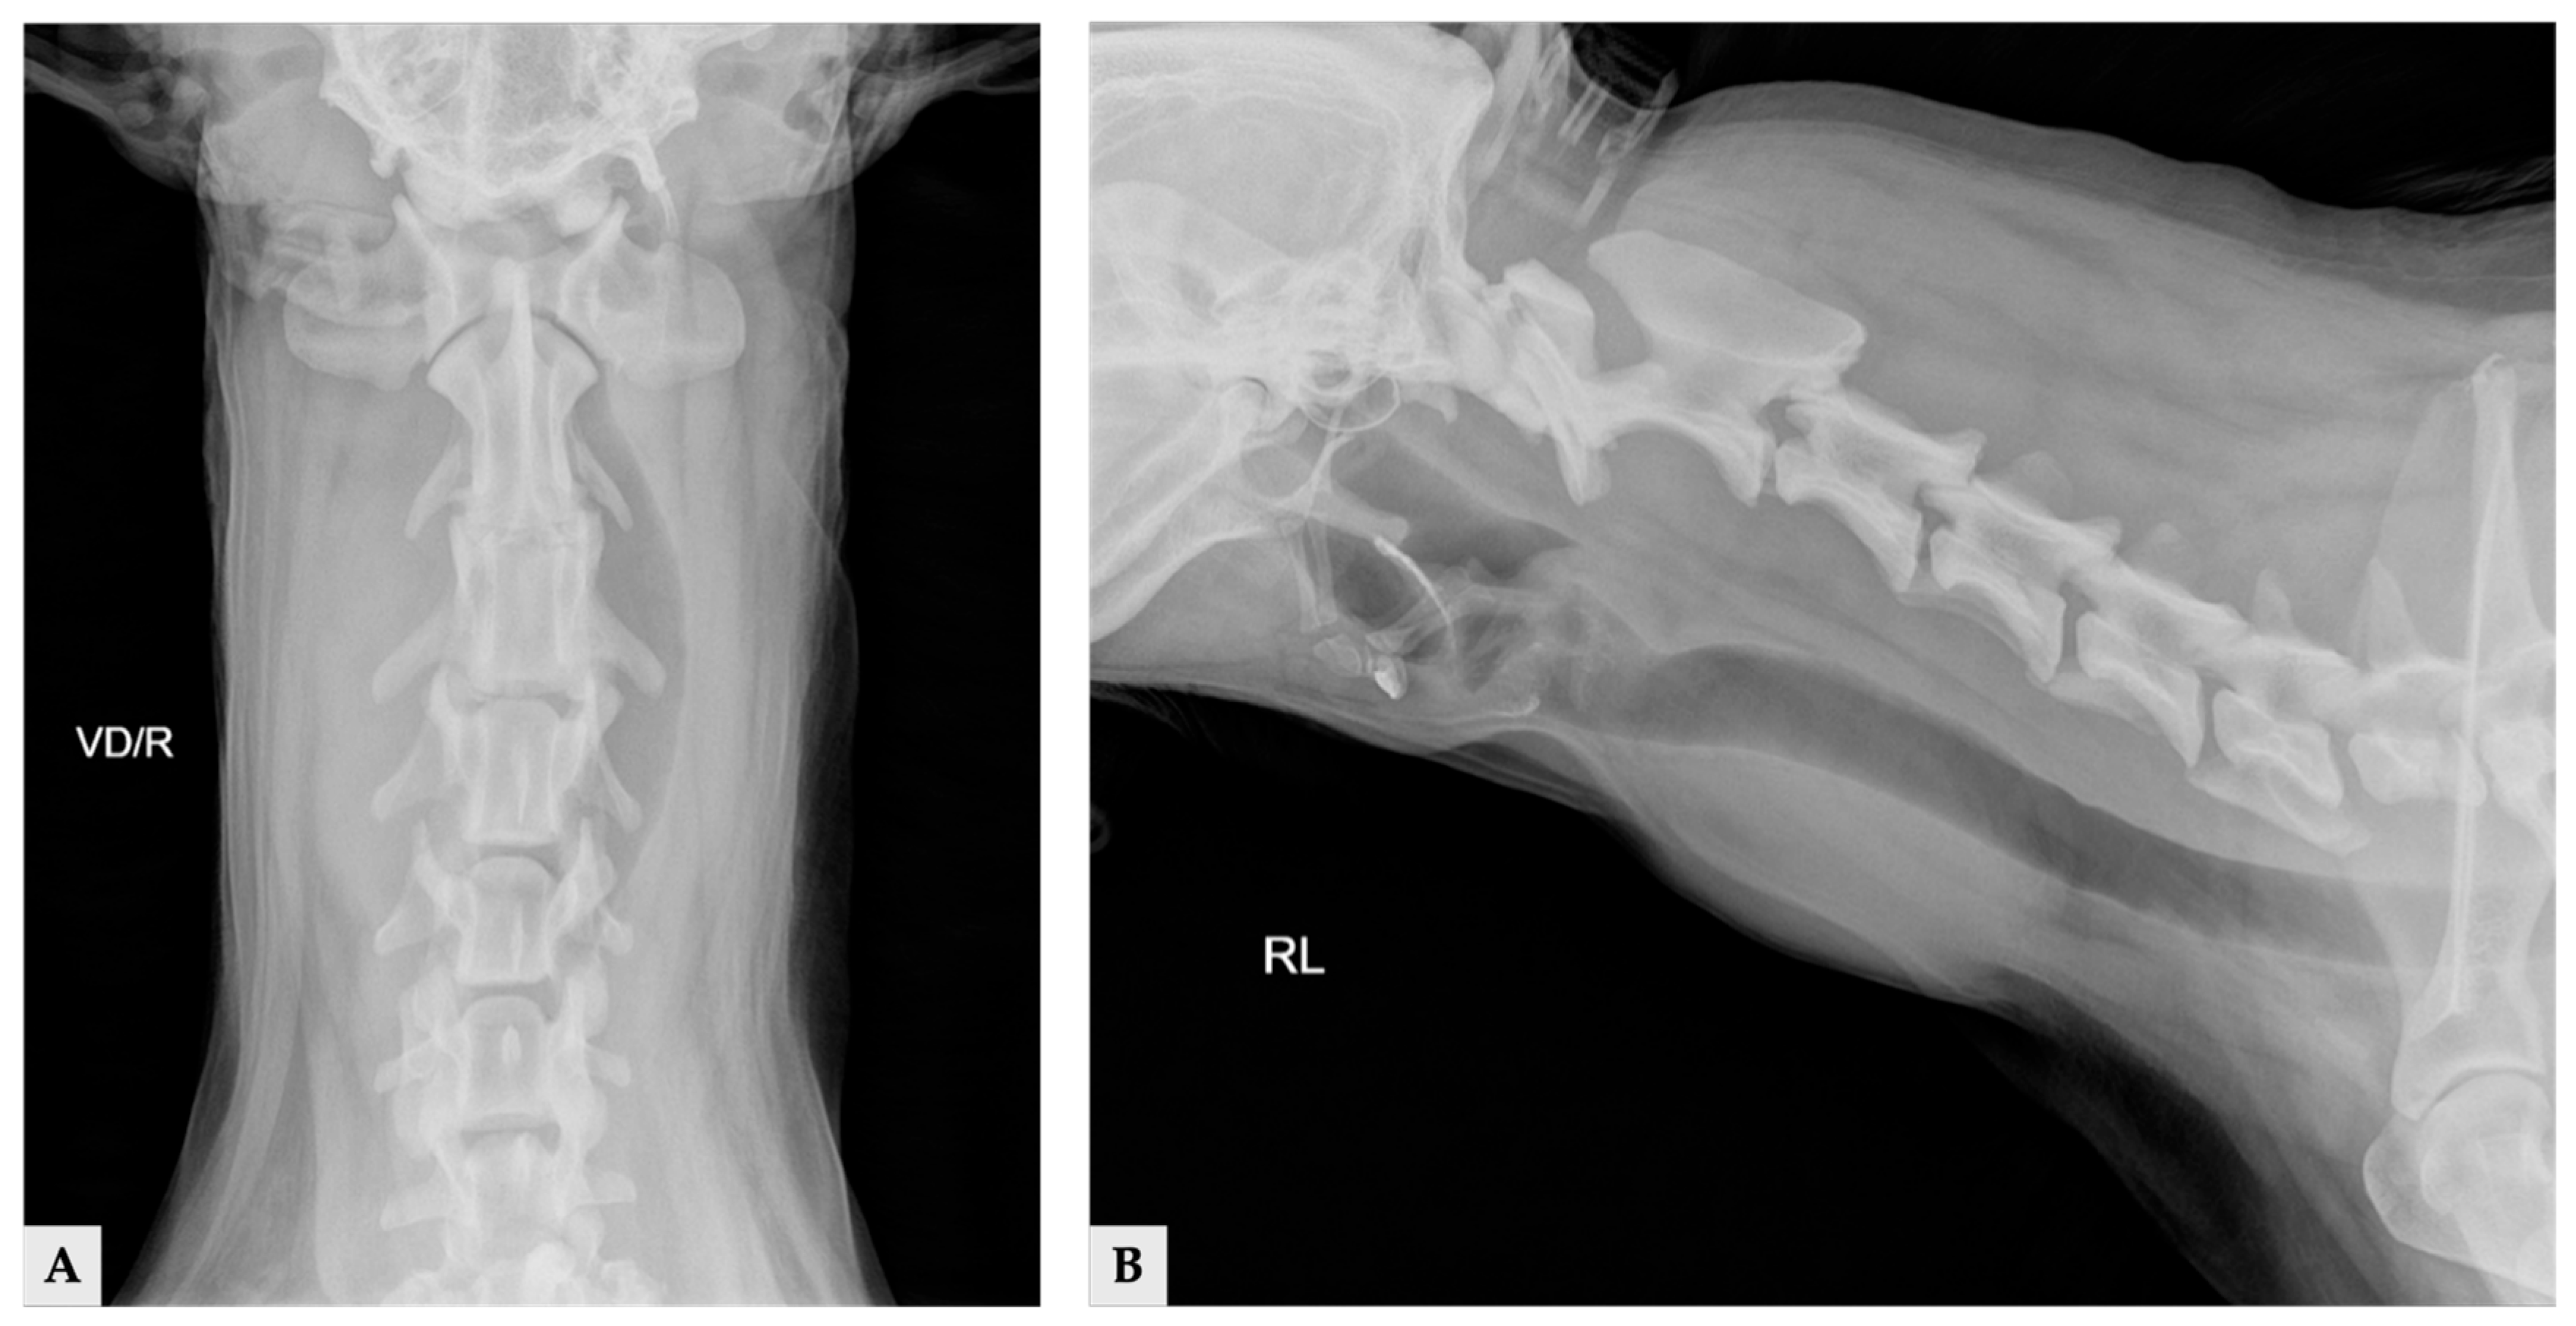

Radiographs demonstrated a soft-tissue opacity over the trachea at the level of C2–C5, causing leftward tracheal deviation (Figure 1). No pulmonary lesions were evident. CT confirmed three well-defined, separate right-sided cervical masses, including the largest palpable cervical mass, extending from the C1 to C5 levels (Figure 2). All three masses were clearly distinct from one another, with no visible continuity on cross-sectional imaging. Mass 1 measured 66.6 mm × 42.0 mm × 37.6 mm (approximately 56 cm3 in volume [14]) and originated from the right thyroid gland. It showed heterogeneous contrast enhancement and produced a filling defect within the adjacent right internal jugular vein, consistent with vascular invasion. Mass 2 measured 25.1 mm × 14.2 mm × 16.5 mm in size, located cranially to mass 1 without any structural connection, and the volume was 3.1 cm3 [14]. Mass 3 measured 11.5 mm × 11.5 mm × 8.6 mm in size, 0.7 cm3 in volume [14] and was positioned between mass 1 and mass2, lying dorsally to mass 2, and was likewise distinctly separated from the other lesions, and the total volume of three masses was approximately 60 cm3 [14]. The left thyroid gland appeared normal, whereas no normal thyroid tissue was identified on the right side at the corresponding anatomical level; instead, only the three masses were present. This finding supports the interpretation that these three lesions originated from the right thyroid gland.

Figure 1.

Cervical radiographic images of the day of presentation: (A) ventrodorsal view; (B) right lateral view.